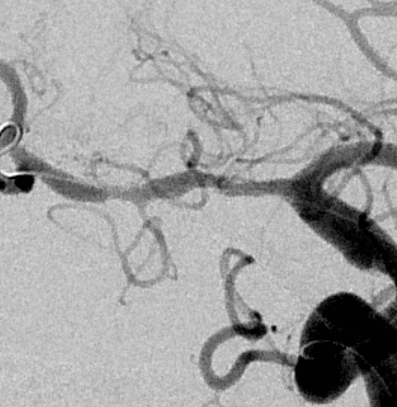

术后1.5个月随访

血管不错

血管进一步改善,继续保守治疗随访

支架进一步打开,直径改善到2.9mm

进一步打开的支架的形态,打开满意